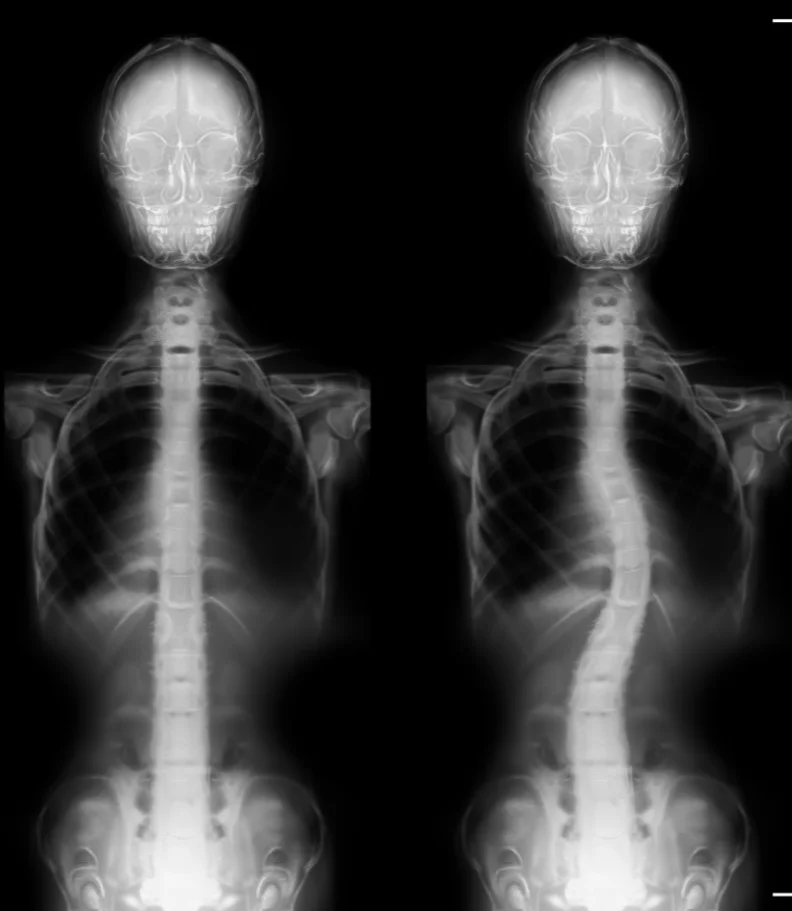

Scoliosis manifests as an abnormal bend or curve in the spine, deviating from the ideal vertical alignment of a healthy spine. The exact origin of this curve can often be elusive. In its early stages, it may begin as a minor bend due to a single vertebra's misalignment. Over time, the body compensates by developing musculature that continues to pull the spine into lateral curves to maintain a level head position.

Often, parents or close associates are the first to notice scoliosis, as the shoulders and pelvis no longer appear level. A thorough physical examination assesses gait and utilizes visual and manual evaluations to determine the extent of spinal curvature. An Adams Position Test, involving the patient bending forward as far as possible, can reveal the presence of an issue. If a noticeable curvature is detected, an X-ray will be employed to assess the severity of scoliosis.